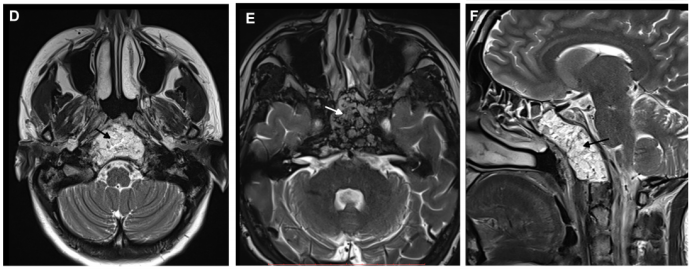

通过单鼻孔入路,福教授为Roger成功完成了手术,术后MRI显示肿瘤被完全切除。术中同样采用了鼻粘膜修复技术,保证了术后的生活质量。

恢复期间,Roger也没有感到鼻部不适。术后2个月随访时,检查显示他鼻窦上方的黏膜转变成健康的粉红色——受损的鼻中隔恢复了正常,顽固性鼻出血症状也完全消失。

术后MRI影像明确肿瘤全切情况,以及用于重建的自体脂肪